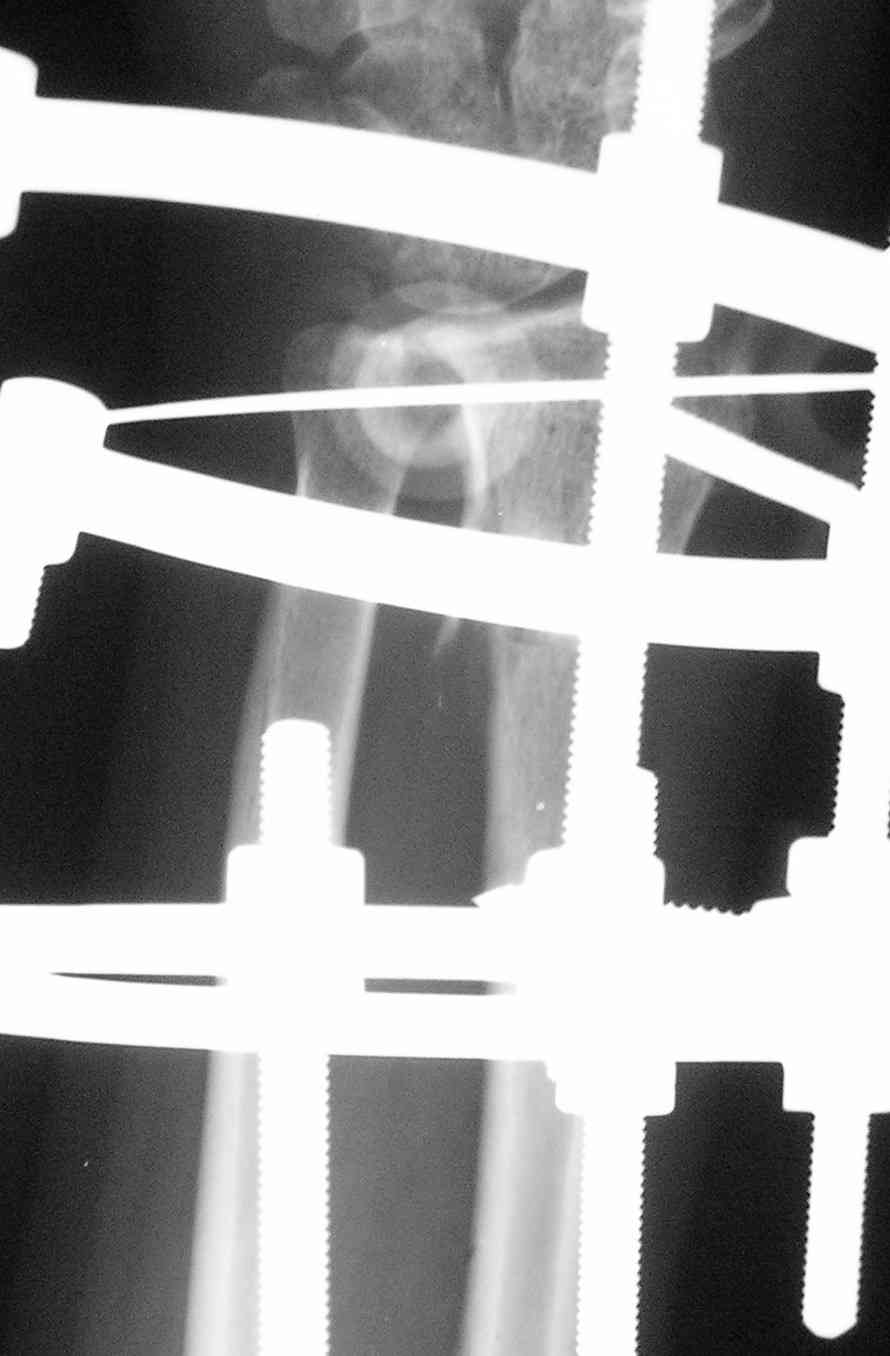

Спице-стержневой аппарат с компактотомией лучевой кости, костная пластика локтевой с удалением пластины. Не комфортно, но больше шансов на благоприятный исход. Заканчиваю лечение с похожей деформацией лучевой кости.